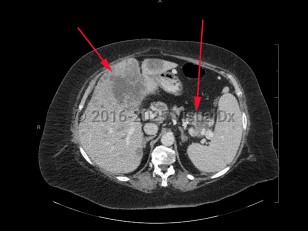

Metastatic pancreatic carcinoma

Metastatic pancreatic carcinoma is cancer arising from the pancreas that has spread to a distant location such as the liver, peritoneum, mesentery, mesenteric lymph nodes, and surrounding vasculature. The majority (95%) of malignant pancreatic carcinoma arises from the exocrine pancreas (related to the pancreatic ductal and acinar cells and their stem cells).

Pancreatic tumors arising from the head and neck of the pancreas (60%-70% of exocrine pancreatic cancers) may spread locally to the celiac axis or the peripancreatic and periportal areas. Pancreatic tumors arising from the tail of the pancreas (20%-25% of exocrine pancreatic cancers) may spread to the common hepatic artery, celiac axis, splenic hilum, or splenic artery. Patients with spread to the mesentery may present with ascites.